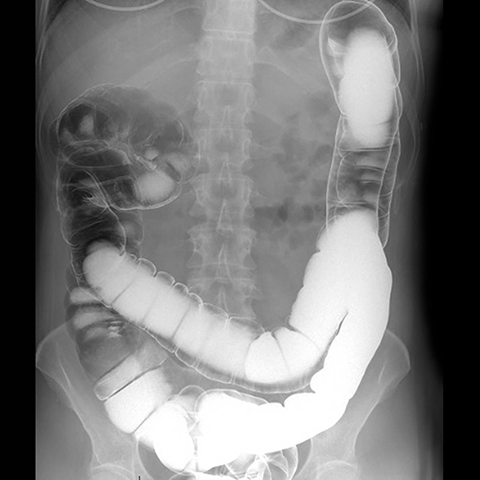

Air constrast barium enema [1 of 2]